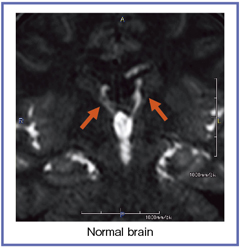

図1は,Time-SLIP法による正常脳の画像だが,正常例において,本来は水頭症の所見であるとされた髄液が第三脳室から側脳室に逆流するreflux flowが観察できる。

図1でも示したように,Time-SLIP法では,正常脳で第三脳室から側脳室への髄液の逆流が認められる。従来の古典的な髄液の循環動態のコンセプトとは異なる動きだが,日常臨床の場では,FLAIR法で側脳室内のフローアーチファクトとしてよく経験される所見である。髄液のフローアーチファクトであり,正常の所見だとされてきたが,教科書にこの部位の髄液の流れについての具体的な記載はなく,Time-SLIP法で初めて描出された動態だと言える。